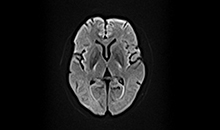

动态B0

涡流补偿技术

改善脂肪抑制效果,减小DWI图像伪影。改善SWI等对B0涡流敏感序列的图像质量